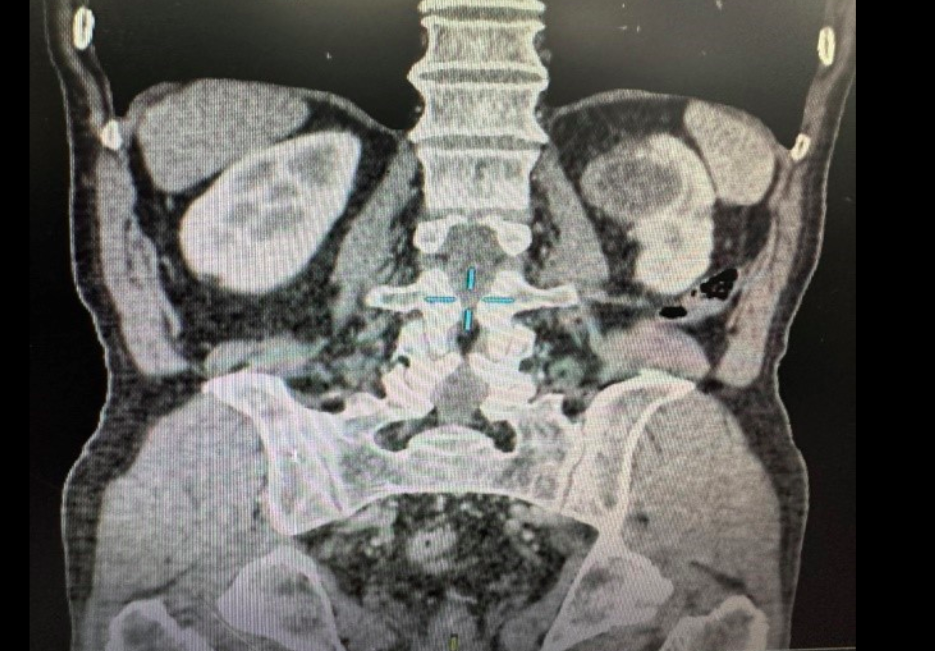

Bệnh nhân vào khoa Tiết niệu trên, Bệnh viện Trung ương Quân đội 108 (Hà Nội) hồi tháng 4. Kết quả hội chẩn của các bác sĩ Bệnh viện 108 đưa ra chẩn đoán ông có nang thận trái Bosniak IV, có nguy cơ ung thư hóa, sỏi niệu quản trái 1/3 trên gây giãn thận độ II.

3 năm trước, nam bệnh từng nội soi niệu quản trái tán sỏi. Lần này, bệnh nhân có chỉ định phẫu thuật cắt bán phần thận trái kèm nang, mổ lấy sỏi niệu quản trái kết hợp 1 thì.

Tiến sĩ Kiều Đức Vinh, khoa Tiết niệu trên, cho biết bệnh nhân vừa có sỏi niệu quản vừa có nang thận Bosniak IV nguy cơ ung thư cao nên các bác sĩ tiến hành phẫu thuật mổ mở, đi đường chéo bên, vào bộc lộ thận và niệu quản trái 1/3 trên, tiến hành lấy sỏi trước. Sau đó, bác sĩ khống chế cuống mạch thận để cắt thận trái bán phần kèm nang và mỡ xung quanh.

Ca mổ kéo dài 90 phút, bệnh nhân không phải truyền máu sau mổ. Tuy nhiên, kết quả giải phẫu mẫu bệnh phẩm cho thấy người đàn ông 59 tuổi bị ung thư biểu mô tế bào sáng của thận độ 1.

Phân loại nang thận theo Bosniak trên hình ảnh CT-scan để tiên lượng nguy cơ ác tính gồm 4 loại.

Cụ thể, loại 1 là nang thận lành tính, loại 2 hiếm khi ác tính, loại 3 nguy cơ ác tính cao (40-50%), loại 4 gần như ác tính (80-100%).